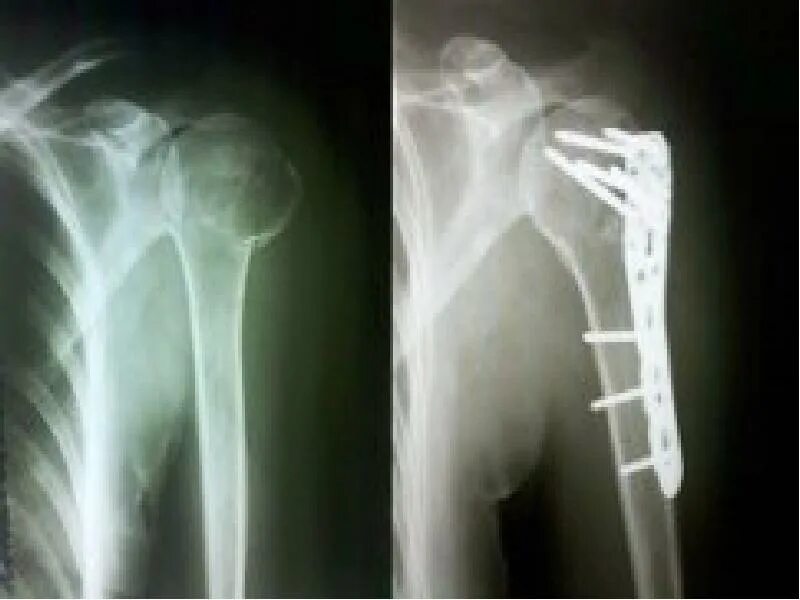

Перелом гребня